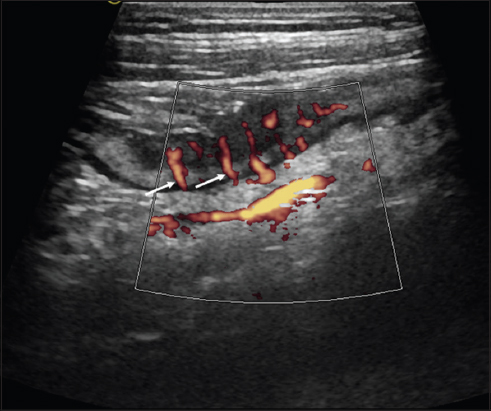

Another characteristic feature of intestinal inflammation and the thickened bowel wall is the increased vascularization, which may be visualized using color Doppler. Increased vascularization is always a sign of active inflammation that correlates with endoscopy, histology, and with the CDAI [6,8,9]. Quantification of vascularization has turned out to be difficult, as vascularization is always dependent on a variety of parameters, including feeding status. A semi-quantitative characterization of vascularization may be made using the simple Limberg score, which divides visible vascularization during color Doppler into four different categories [10] (Fig. 3).

thumblarge

Figure 3 Longitudinal view of the terminal ileum in ileal Crohn’s disease with Power Doppler (10 MHz probe) “Comb sign”: parallel mesenteric vessels as a sign of severe inflammation (Limberg Score 4) (arrows)